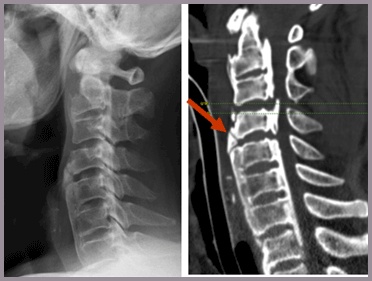

이 사건의 의뢰인은 상대방이 동석한 교통사고 피해자로서 사고 후 요통으로 ○○병원 응급실에 내원하였고 “제2요추폐쇄증후군” 진단을 받았다. 방사선 검사에서 “압박 골절”이 나타났습니다. 부상 초기에 척추의 추가 기형이 진행되거나 신경학적 증상이 나타나면 수술을 준비하고 며칠 동안 경과를 지켜보십시오. 다행스럽게도 통증은 신경학적 증상 없이 차차 가라앉았고, 정형외과를 통한 보존적 치료만이 상당 기간 지속되다가 치료가 종료되었다.

응급실 기록

진단